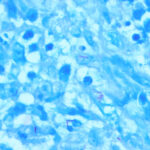

Severely immunocompromised patients, such as those with HIV infection, have a very high prevalence of M. aviumintracellulare bacteremia , and many show one or more cutaneous papules and nodules . Steroid therapy also predisposes to skin lesions. The histology may be granulomatous or mixed acute and chronic inflammatory, as with tuberculosis . Sometimes, there is a histology resembling that of lepromatous leprosy .Macrophages contain large numbers of bacilli without necrosis, and a spindle cell transformation of macrophages, forming a histoid-like lesion (as in leprosy), can occur . |

Histopathology. The infection begins as a subcutaneous nodule exhibiting "ghost" ischemic-type dermal collagen and fat necrosis with deposition of fibrin and hematoxyphilic extracellular clumps of mycobacteria. Ulceration proceeds as the epidermis loses its vascular supply. Ziehl-Neelsen stains reveal vast numbers of acid-fast bacilli in the necrotic fat ; their distribution is often irregular. A variable degree of neutrophil infiltration and thrombosis of vessels are also observed. In time, a nonspecific granulation tissue or a granulomatous reaction commences from the depth and sides of the ulcer; healing and re-epithelialization take place with considerable scarring. Acid-fast bacilli decline rapidly in number during healing . The histopathologic case definition for Buruli ulcer, useful for research studies, is (a) the typical pattern of infarctivelike necrosis of deep dermal collagen and fat and (ideally, but not always found in limited samples) (b) nearby clusters of acid-fast bacilli. |